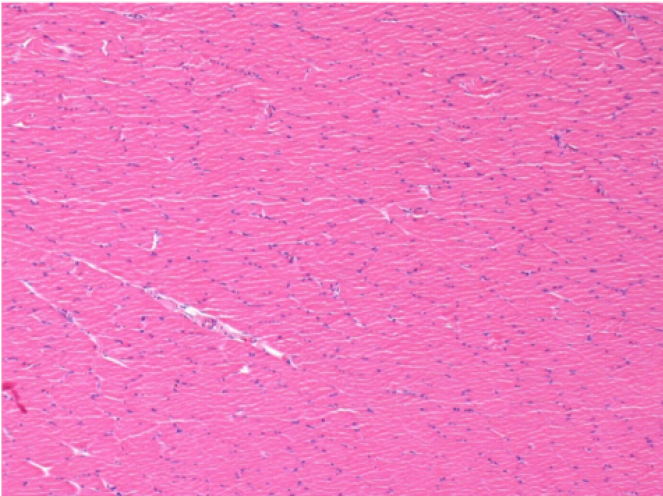

09

سبعة أشهر بعد حقن إندوبيل

7 أشهر (D210) بعد حقن Endopeel IM 0.1 مل في العضلة أمام الظنبوب اليمنى.

Complete Restitutio ad integrum after 7 months

L : Control-100xD210

R:100xD210

L :Control 50xD210

R50X-D210